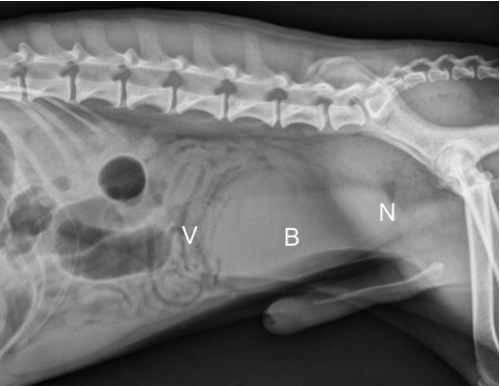

what combo of imaging modalities is the best way to view ectopic ureters

negative contrast cystogram (make bladder black) + EU (highlight ureters)

female dog with history of incontinence since birth

ectopic ureters

normal non-distended bladder

hydroureter

accumulation of contrast not in bladder

abnormal termination location of ureters

ureters and kidneys may appear normal - trace to abnormal termination site

± hydroureter/hydronephrosis if cause obstruction